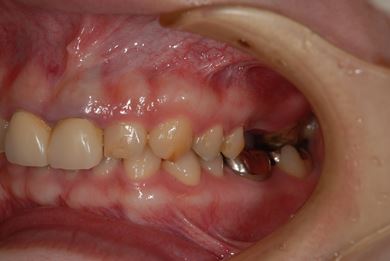

| 性別/年齢 | 女性 / 30歳 | ||||||||||||||||||||||||||||||||

| 主訴 | 上の奥歯を抜歯すべきかどうか、抜歯する場合はインプラント治療が可能かどうかの相談。 | ||||||||||||||||||||||||||||||||

| 治療方針 | ソケットリフトにて上顎洞を拳上し、インプラント治療を可能にする。 | ||||||||||||||||||||||||||||||||

| 治療内容 | インプラント2本(ソケットリフト)、メタルボンドセラミッククラウン1本 | ||||||||||||||||||||||||||||||||